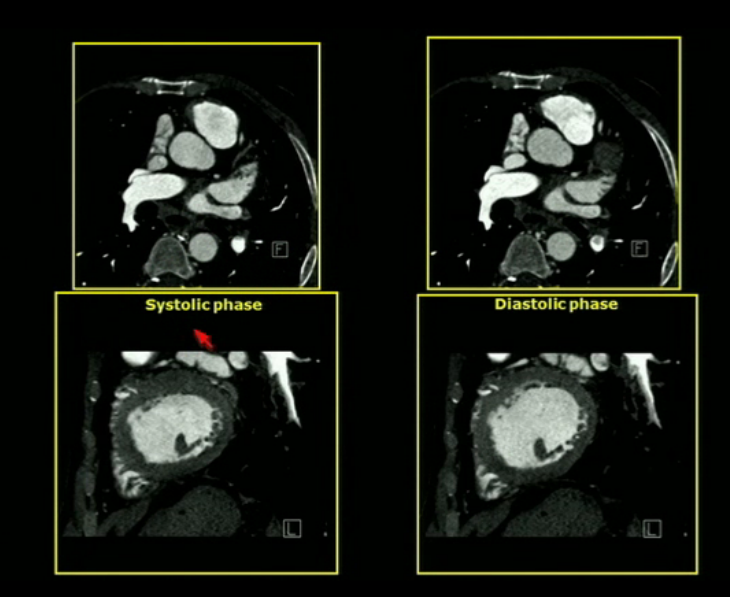

Short axis view of the human heart. Top systole. Bottom diastole. A Movement Artifact At Diastole The precorrection image (a) shows an artifact in the lad (arrow) due to the acquisition band falling in late diastole/early. Misregistration artifacts, which appear as. Often this technique is conveyed to. Coronary ct angiography is a novel noninvasive imaging technology that provides a unique view of cardiac and coronary artery pathologies. While waiting for this magnetisation nulling, due to. Cardiac. Movement Artifact At Diastole.